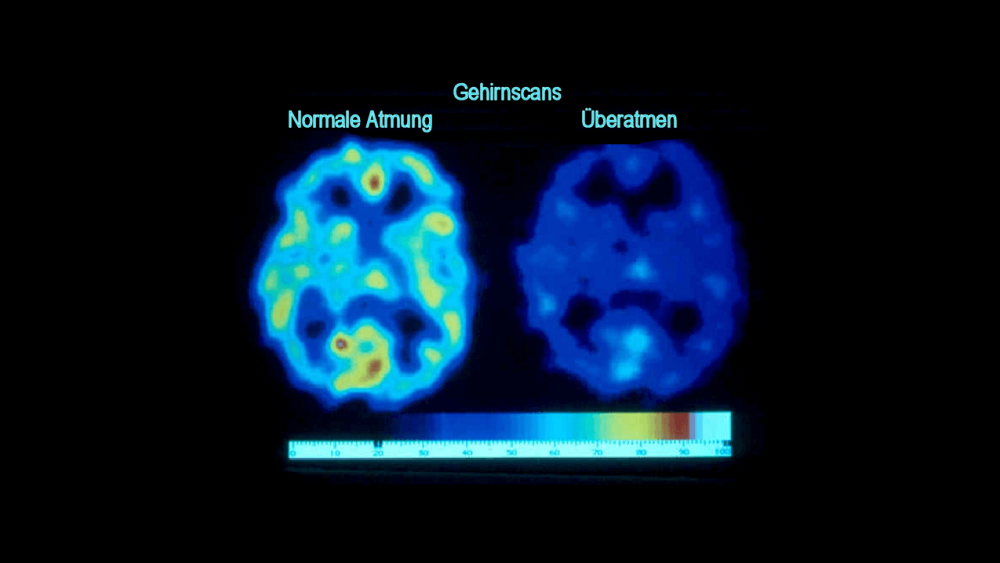

Niedrige Kohlendioxidgehalte haben eine Reihe von nachteiligen Auswirkungen auf die Physiologie, z.B. Sauerstoffmangel, wie in diesem Gehirn-Scan gezeigt, der zu Schäden und Symptomen führt.